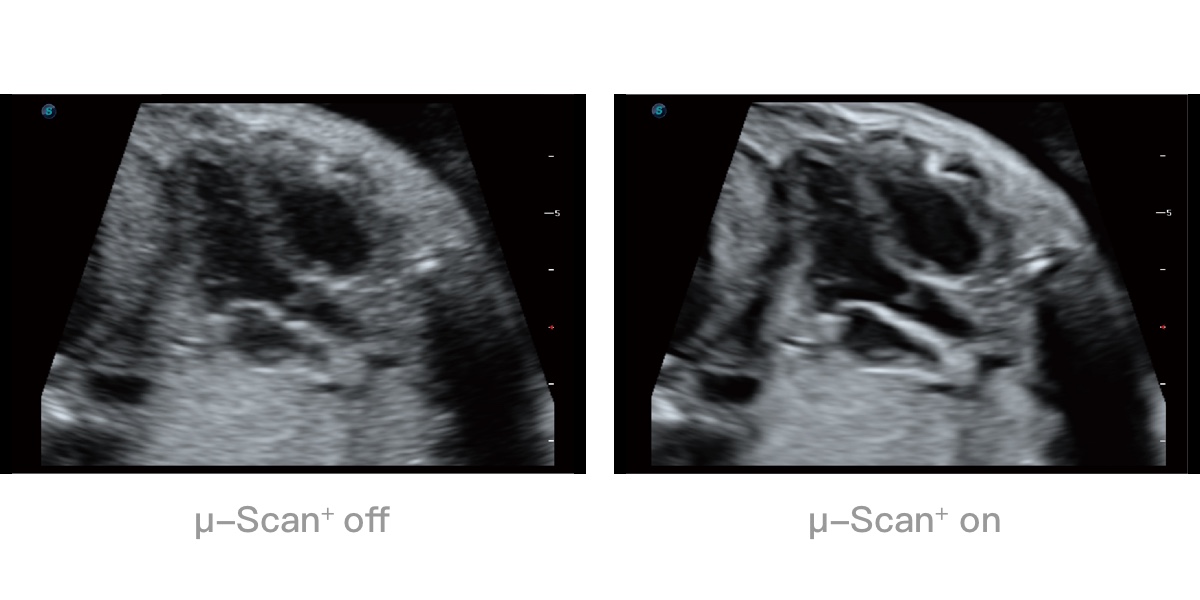

微米成像技术提升了对组织斑点噪声信号的抑制能力,并进一步强化边界信息,从而获得清晰图像。

0.5mm厚度的薄层切片显像,可清晰显示微小病灶的连续断面。

可同时显示组织结构表面和内部的轮廓信息,达到透视效果,为临床提供更丰富的诊断信息。